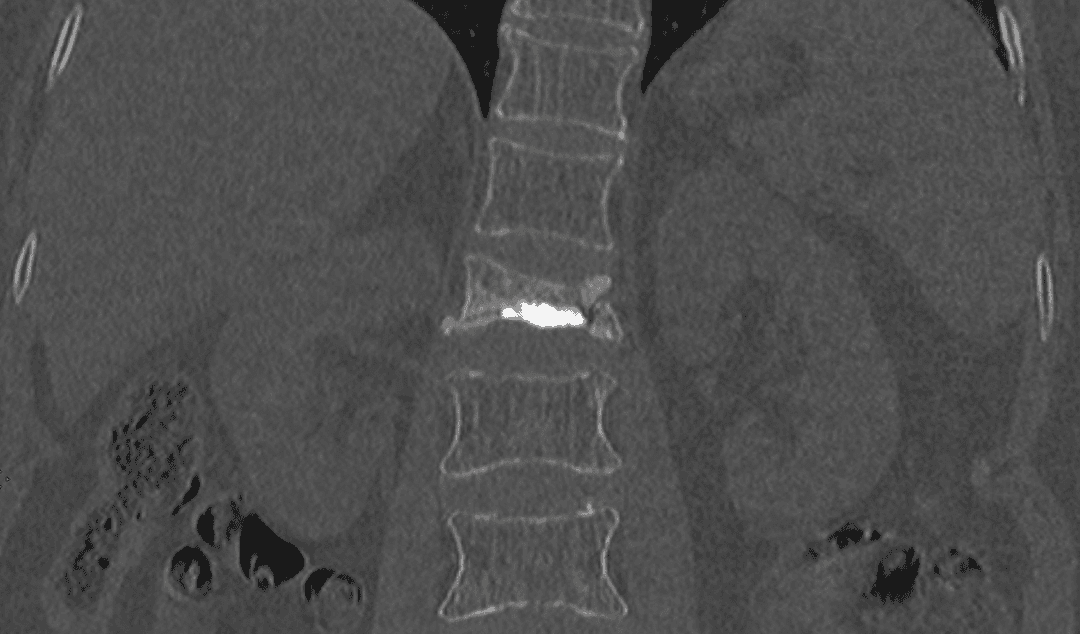

Scanner

Scanner montrant une fracture d'une vertèbre